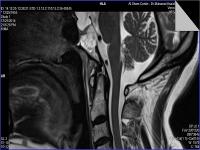

Medical imaging is an important investigative tool will help doctors to reach for the diagnosis of certain diseases, and the the advanced and high-quality imaging technologies are an important factor in maintaining the health of patients and accurate diagnosis of pathological lesions.